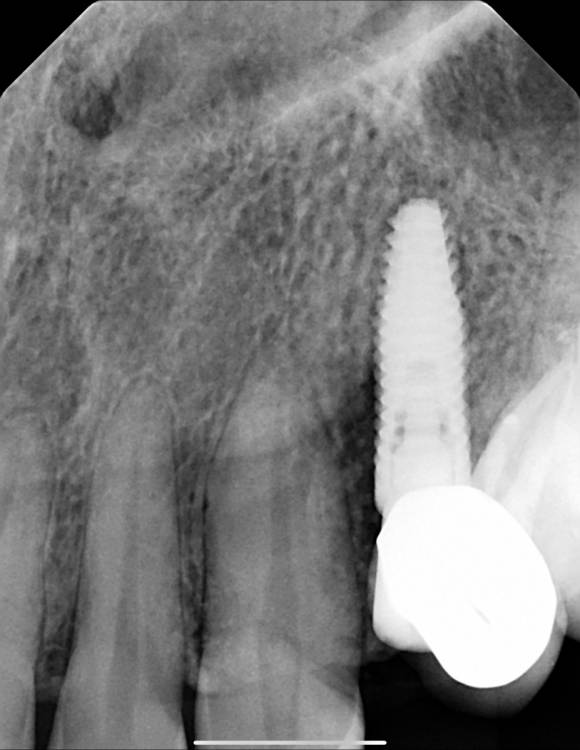

lola-1234 Опубликовано 13 декабря, 2021 Автор Поделиться Опубликовано 13 декабря, 2021 08.12.2021 в 23:13, Irouil сказал: Я бы посоветовал попробовать ещё одну консультацию на стороне получить - теперь, когда формирователь уже установлен, очный осмотр даст больше возможности для диагностики. Была у ещё одного хирурга, он сказал что по снимку видно буд-то от импланта отошла кость. Имплант не шатается. Возможно имплант можно ещё спасти, пролечить воспаление. Но это нужно снимать формирователь и смотреть. Пойду скоро к своему хирургу. Ссылка на комментарий

Irouil Опубликовано 13 декабря, 2021 Поделиться Опубликовано 13 декабря, 2021 (изменено) @lola-1234 Я хочу сказать, что Ваш снимок (последний) выглядит неоднозначно. Есть выраженная радиопрозрачность (потемнение на снимке) между зубом и имплантом, что может говорить о его «неполной» интеграции. Проверить это можно только так, как описывает @Bier - попробовать его выкрутить с определенным усилием. Если имплант его не выдерживает, то спасать там нечего - он все равно Вас подведёт, лучше раньше, чем позже. Очень часто врачи не проверяют интеграцию имплантов инструментально (так, как описано выше) и очень редко, но могут быть ложно-отрицательные результаты - имплант вроде стоит крепко, не шатается, но после протезирования через короткое время подводит. Именно поэтому мы тут обсуждаем эту важную, но очень маленькую деталь - проверку «торком». Тем не менее, на этом же снимке вдоль шейки зуба со стороны импланта видна костная ткань, что может говорить о простом артефакте снимка в том месте, которое выглядит как «отошедшая кость» - возможно, что и имплант интегрирован, и все вообще там здорово. Тогда нужно будет его протезировать, смысла удалять его уже не будет, скорее всего он проблем не вызывает. Но, в такой ситуации, до протезирования я бы сходил на Вашем месте к неврологу и поискал бы вместе с доктором причину болей. Изменено 13 декабря, 2021 пользователем Irouil 1 Ссылка на комментарий